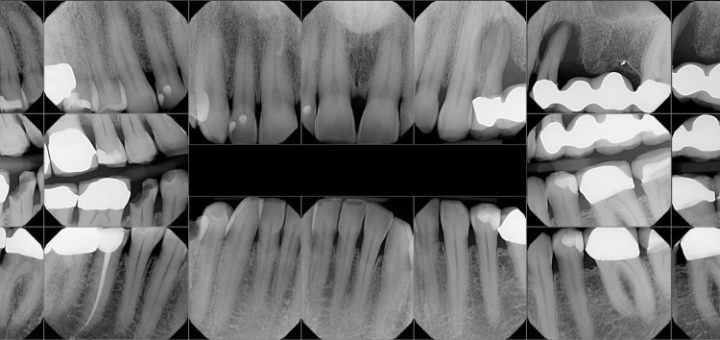

Full Mouth Reconstruction Full Mouth Reconstruction, also termed as Full Mouth Rehabilitation or Full Mouth Restoration, is a procedure of of rebuilding and restoring the teeth in the upper and lower jaws. The procedure...